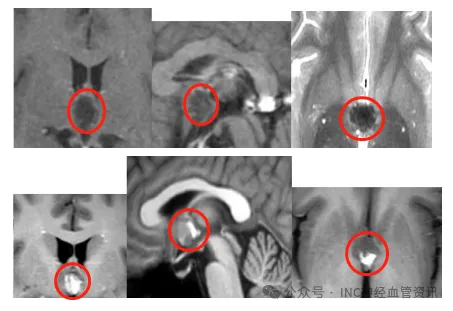

3岁女童脑干海绵状血管瘤术后,医生为什么坚持给她父母也做基因检测?

INC国际巴教授所在研究团队曾报道过一个病例:患者是3岁小女孩,因突发头痛、嗜睡、偏瘫等症状而紧急就医,检查结果发现小朋友脑袋里不仅有个很大的海绵状血管瘤,而且还存在多出病灶...